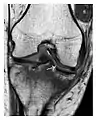

a

b

c

Figure 1: A 56-year-old woman presenting with left knee pain after a fall. (a) Initial anteroposterior radiograph was considered normal, however, subtle cortical disruption of the anterior rim of the medial tibial plateau, medial to the tibial spine, is noted (arrow). (b) Coronal T1-weighted MRI confirms the cortical disruption (arrow) and shows extensive fracture through the proximal tibia. (c) Coronal proton density-weighted image with fat saturation shows extensive edema in the subchondral bone. Note also hypersignal adjacent to the medial collateral ligament corresponding to a grade I sprain (arrowheads).[1]